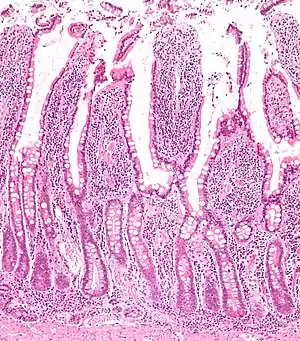

The three sections of the small intestine look similar to each other at a microscopic level, but there are some important differences. The parts of the intestine are as follows:

| Mucosa: intestinal epithelium | Simple columnar. Contains goblet cells, Paneth cells | Similar to duodenum, but the intestinal villus is long | Similar to duodenum, but the intestinal villus is short |

Digested food is now able to pass into the blood vessels in the wall of the intestine through either diffusion or active transport. The small intestine is the site where most of the nutrients from ingested food are absorbed. The inner wall, or mucosa, of the small intestine, is lined with intestinal epithelium, a simple columnar epithelium. Structurally, the mucosa is covered in wrinkles or flaps called circular folds, which are considered permanent features in the mucosa. They are distinct from rugae which are considered non-permanent or temporary allowing for distention and contraction. From the circular folds project microscopic finger-like pieces of tissue called villi (Latin for "shaggy hair"). The individual epithelial cells also have finger-like projections known as microvilli. The functions of the circular folds, the villi, and the microvilli are to increase the amount of surface area available for the absorption of nutrients, and to limit the loss of said nutrients to intestinal fauna.